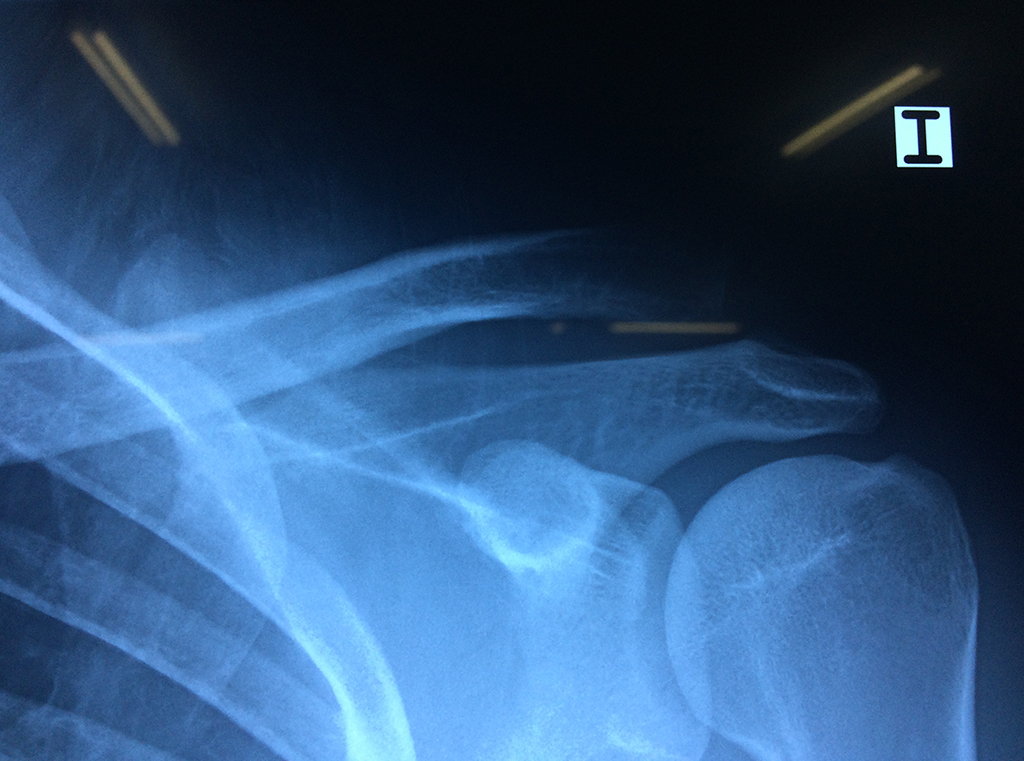

La principal articulación del hombro es la que une la cabeza del húmero con la escápula, recibe el nombre de articulación escapulohumeral y presenta dos superficies articulares, una de ellas corresponde a la cabeza del humero que tiene forma semiesférica y la otra es la cavidad glenoidea de la escápula, estas superficies están recubiertos por cartílago que permiten un movimiento suave e indoloro.